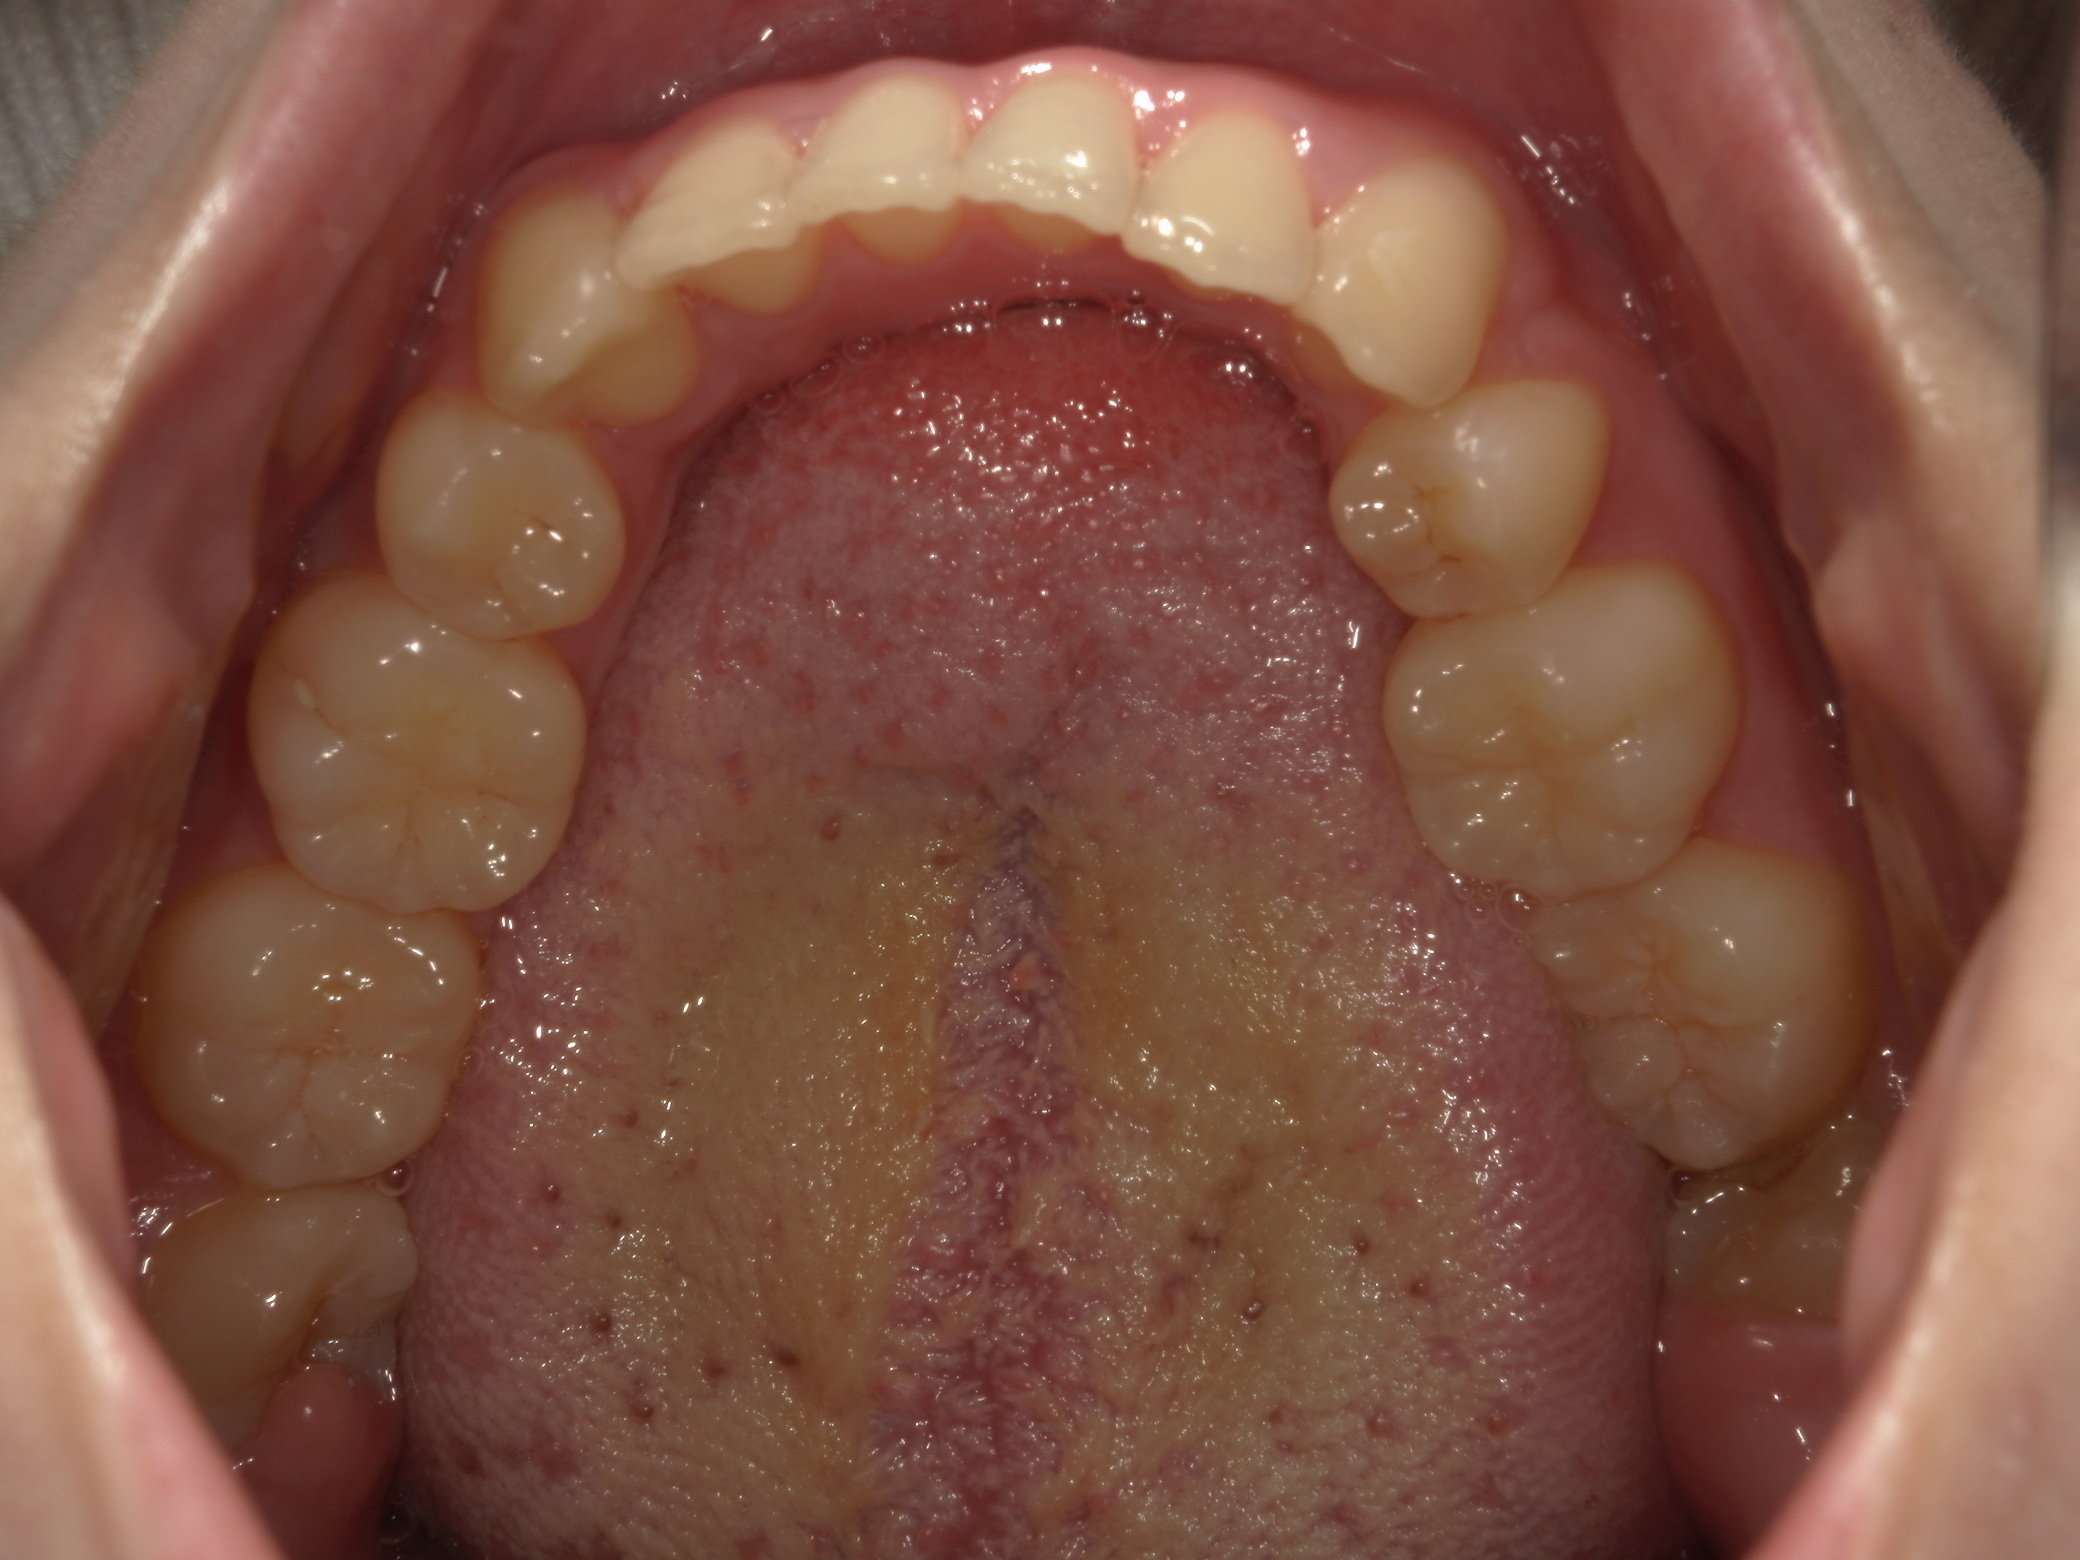

咬み合わせが逆であること(反対咬合)が気になる

| 年齢・性別 | 15歳 女性 |

|---|---|

| 主訴 | 咬み合わせが逆であること(反対咬合)を気にされて来院された女性。見た目や機能面の改善を希望されていました。 |

| 治療期間・回数 | 4年4ヶ月・28回 |

| 費用 | 900,000円 |